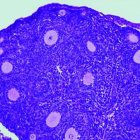

Ratones de laboratorio utilizados en los experimentos.